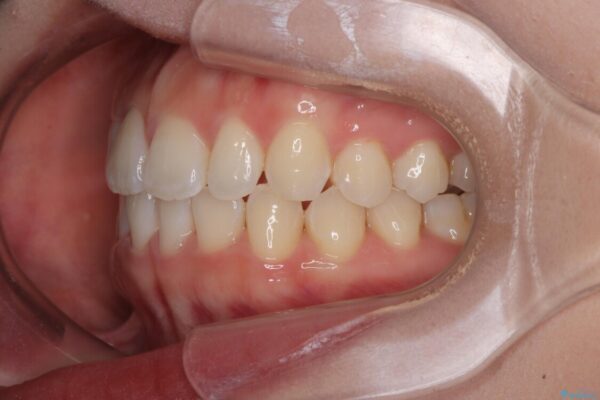

前歯のデコボコが気になるでのことで来院された患者様です。

歯列アーチが狭くスペース不足により前歯がデコボコしている状態でした。見た目を改善しつつ、前歯を前方に突出させず、自然な笑顔を目指したいというご希望でした。

治療前

• 目立ちにくい表側装置で1年完了!狭いアーチを側方拡大し前歯のデコボコを整えた症例 治療前画像